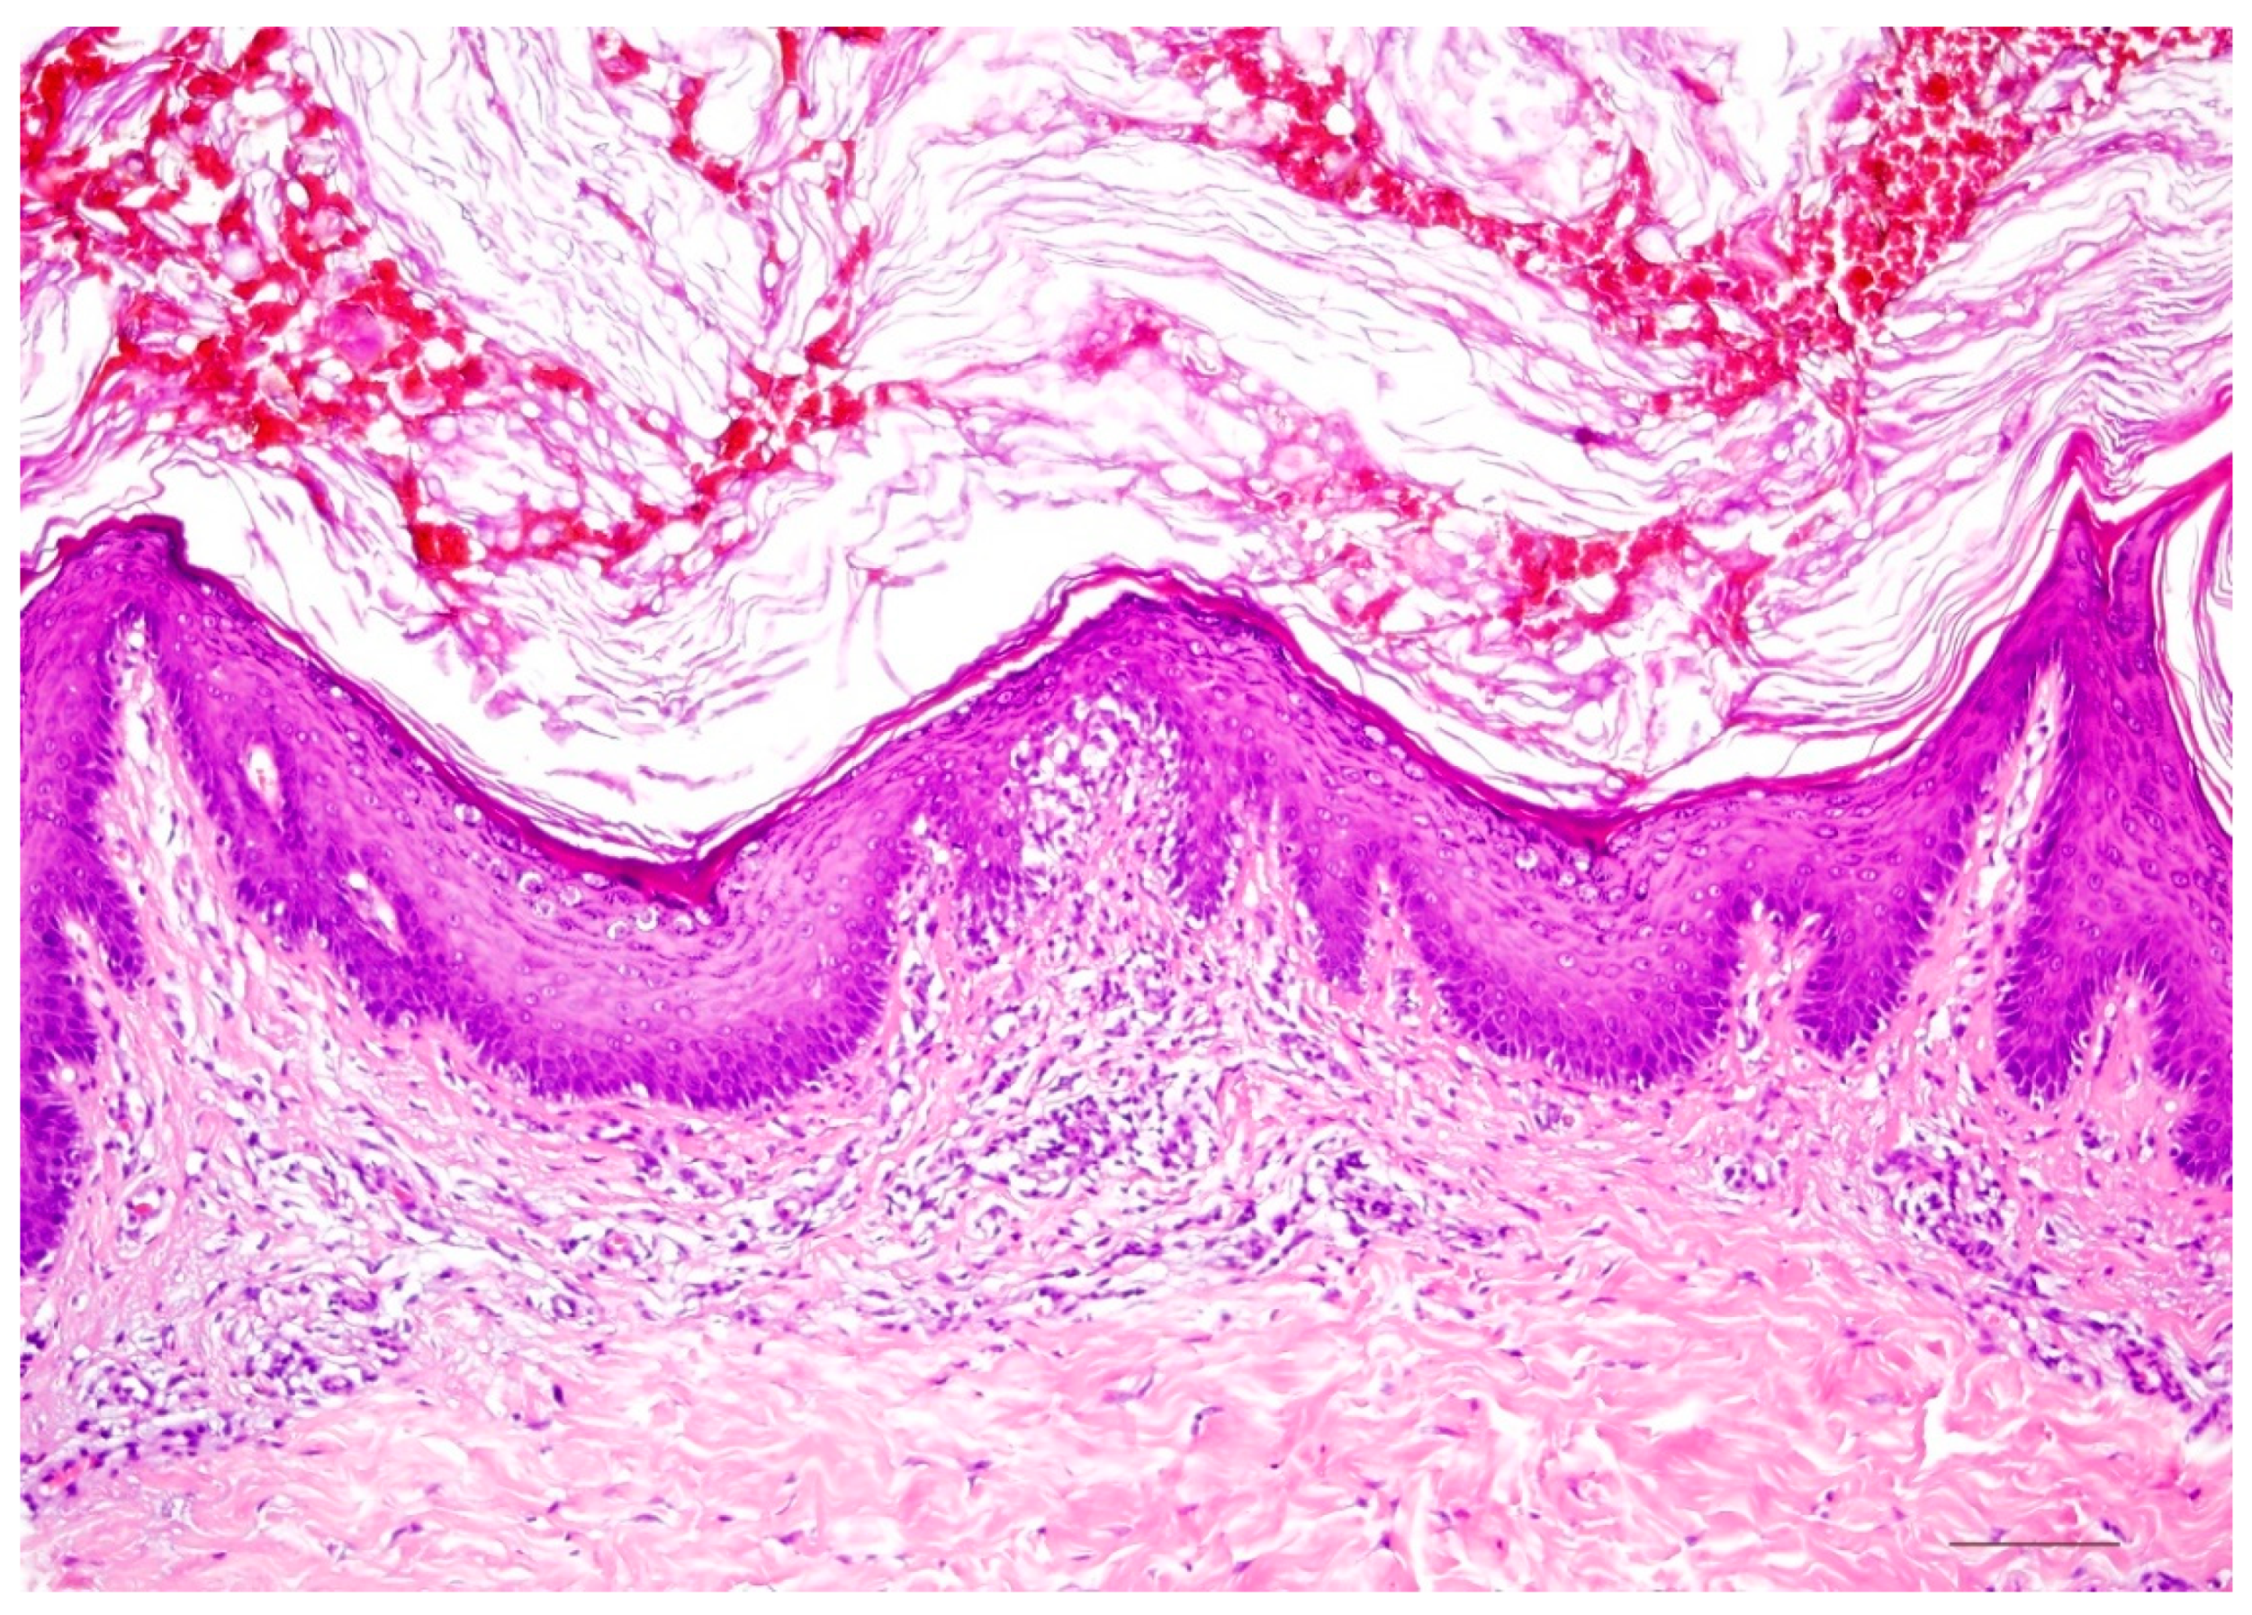

4. Autosomal Recessive Congenital Ichthyosis

4.1. Histology